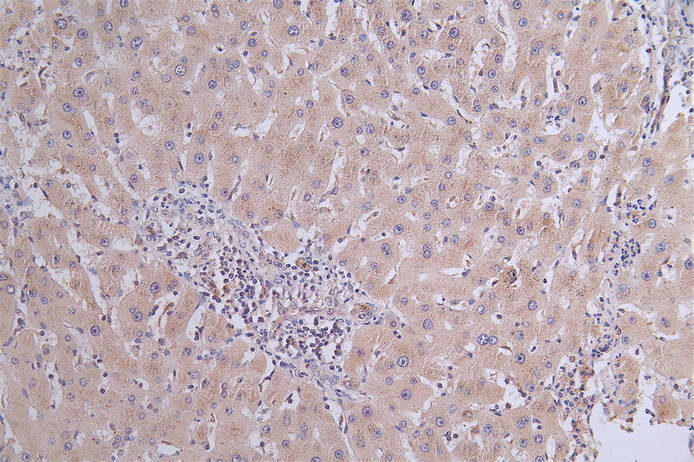

IHC image of CSB-RA119753A0HU diluted at 1:50 and staining in paraffin-embedded human liver cancer performed on a Leica BondTM system. After dewaxing and hydration, antigen retrieval was mediated by high pressure in a citrate buffer (pH 6.0). Section was blocked with 10% normal goat serum 30min at RT. Then primary antibody (1% BSA) was incubated at 4°C overnight. The primary is detected by a Goat anti-rabbit polymer IgG labeled by HRP and visualized using 0.31% DAB.